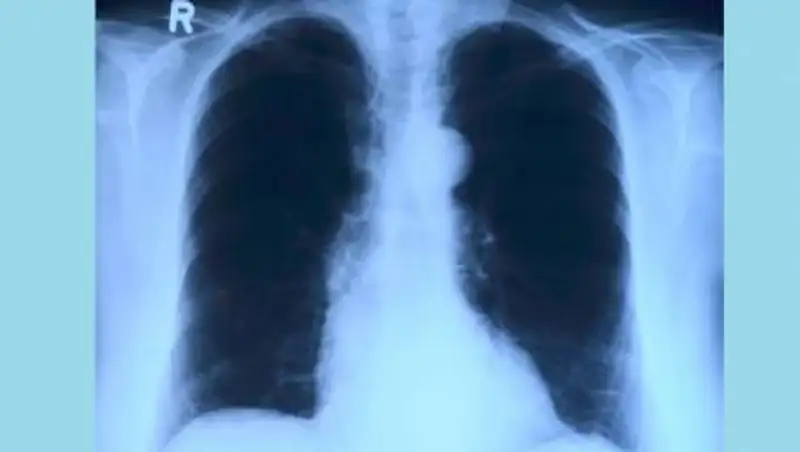

Если у пациента кашель более 2-х недель, резкое похудание, потливость, боли в грудной области, кровохарканье (не во всех случаях), слабость, быстрая утомляемость, повышение температуры тела. то это вероятные симптомы туберкулеза. Это инфекционное заболевание, вызываемое микобактериями туберкулеза, больше известными как бациллы или палочки Коха. Поражаются преимущественно легкие(80%) реже другие органы (20%). Ранняя диагностика и своевременное лечение - ключевой момент в борьбе с туберкулезом. - сказала врач-фтизиатр поликлиники ГКБ №7 Алматы Каракоз Утемуратова.

Туберкулез остается одной из самых смертоносных инфекций и одной из ведущих причин смертности населения в мире. Согласно информации ВОЗ от туберкулеза ежедневно погибает в мире около 4000 человек. В Казахстане с каждым годом регистрируется все меньше случаев заболевания туберкулезом, и уровень смертности среди больных продолжает падать. Но туберкулез не исчез. Общее число пациентов, страдающих от туберкулеза, все еще высоко.